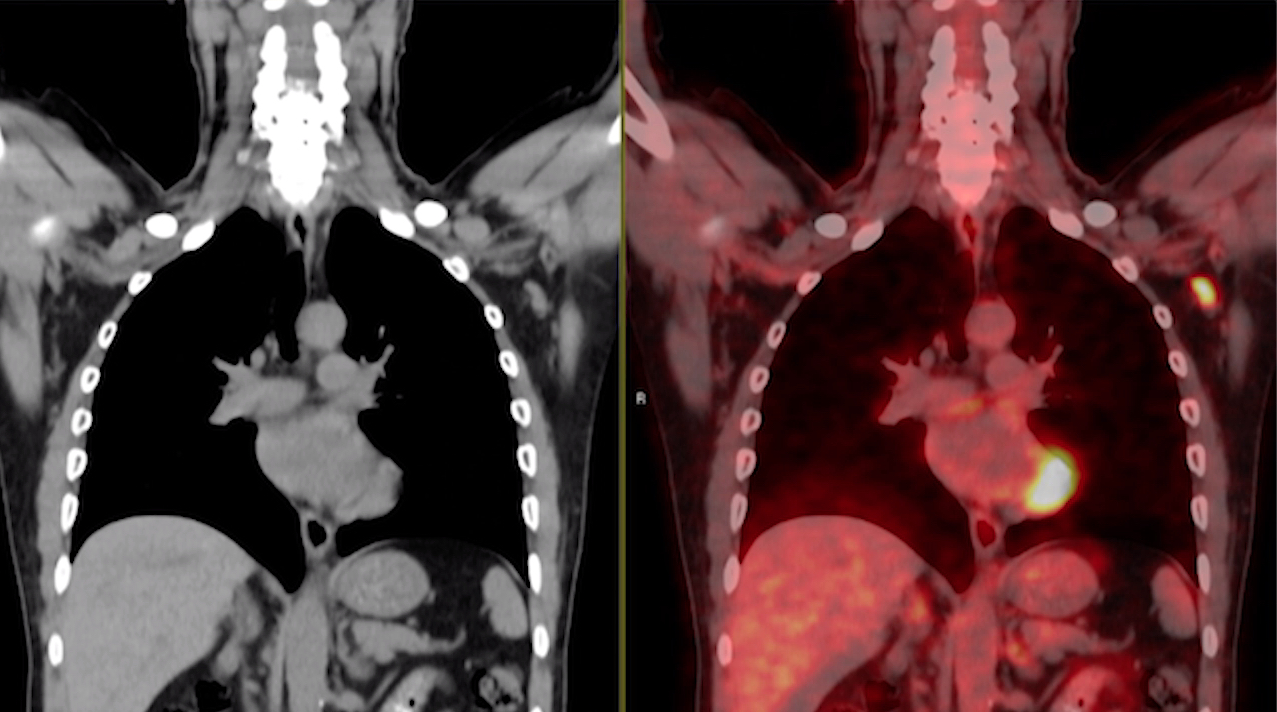

This photo gallery shows the variety of radiological presentations of COVID-19 (SARS-CoV-2) in medical imaging, including computed tomography (CT), radiograph X-rays, ultrasound, echocardiograms and magnetic resonance imaging (MRI). The radiology images show examples of typical COVID pneumonia in the lungs and the numerous complications the virus causes in the body in multiple organs, including the brain, kidneys, heart, abdomen and vascular system.